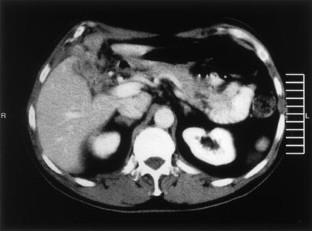

In the present case the inflammation involved all the layers of the gallbladder, the surrounding connective tissue, and part of the right lobe of the liver and right transverse colon. The clinical and radiological findings were suggestive of advanced carcinoma of the gallbladder. However, intraoperative frozen section investigation revealed xanthogranulomatous cholecystitis, for which simple cholecystectomy is the treatment of choice.

Fig. 1.

Fig. 2a, b.

Fig. 3.